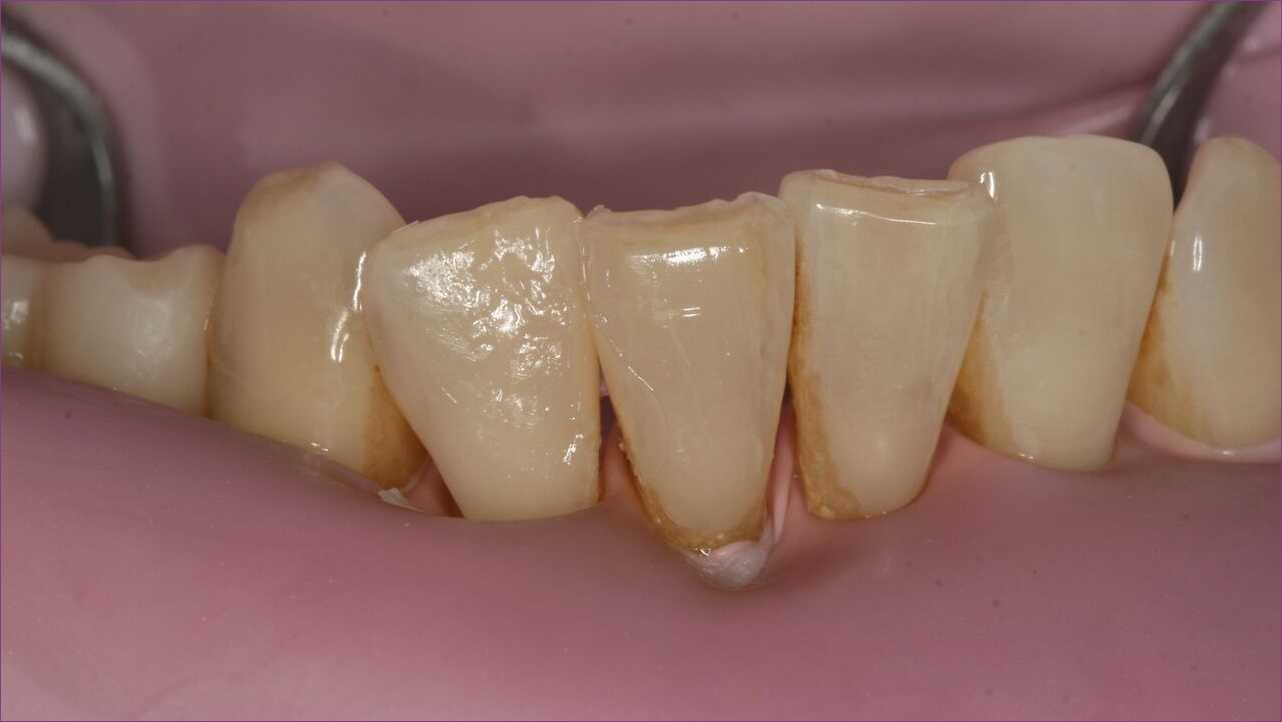

Páciensünk, egy kedves, mosolygós középkorú hölgy arra kért minket, hogy alsó frontfogain keletkezett fogszuvasodást orvosoljuk, mégpedig úgy, hogy a végeredmény ne legyen szembetűnő.

A metszőfogak szuvasodásának több oka is lehet, leggyakoribb a fogköztisztítás elhanyagolása, a fogmosás helytelen technikája, az összetorlódott fogak miatt nehezen tisztítható felületek. Páciensünk esetében mind a három tényező fennállt.

Mivel a frontfogak beszéd és mosolygás közben is igencsak szem előtt vannak, a kezelőorvos a láthatatlan kompozittömés mellett döntött.

A kompozittömés manapság a legmodernebb és egyben legesztétikusabb tömésfajtának számít. Az anatomikus felépítésnek köszönhetően a fog eredeti funkciója teljes mértékben helyreállítható. A kezelést ezúttal úgynevezett kofferdamizolációban végeztük, mivel a korszerű tömések nagyon érzékenyek a nedvességre. A gondosan elhelyezett gumilepedő távol tartja a nyálat és az egyéb nedvességforrásokat a kezelt területtől. Ráadásul megakadályozza, hogy bármi a torokba kerüljön, például az apró amalgámdarabok.